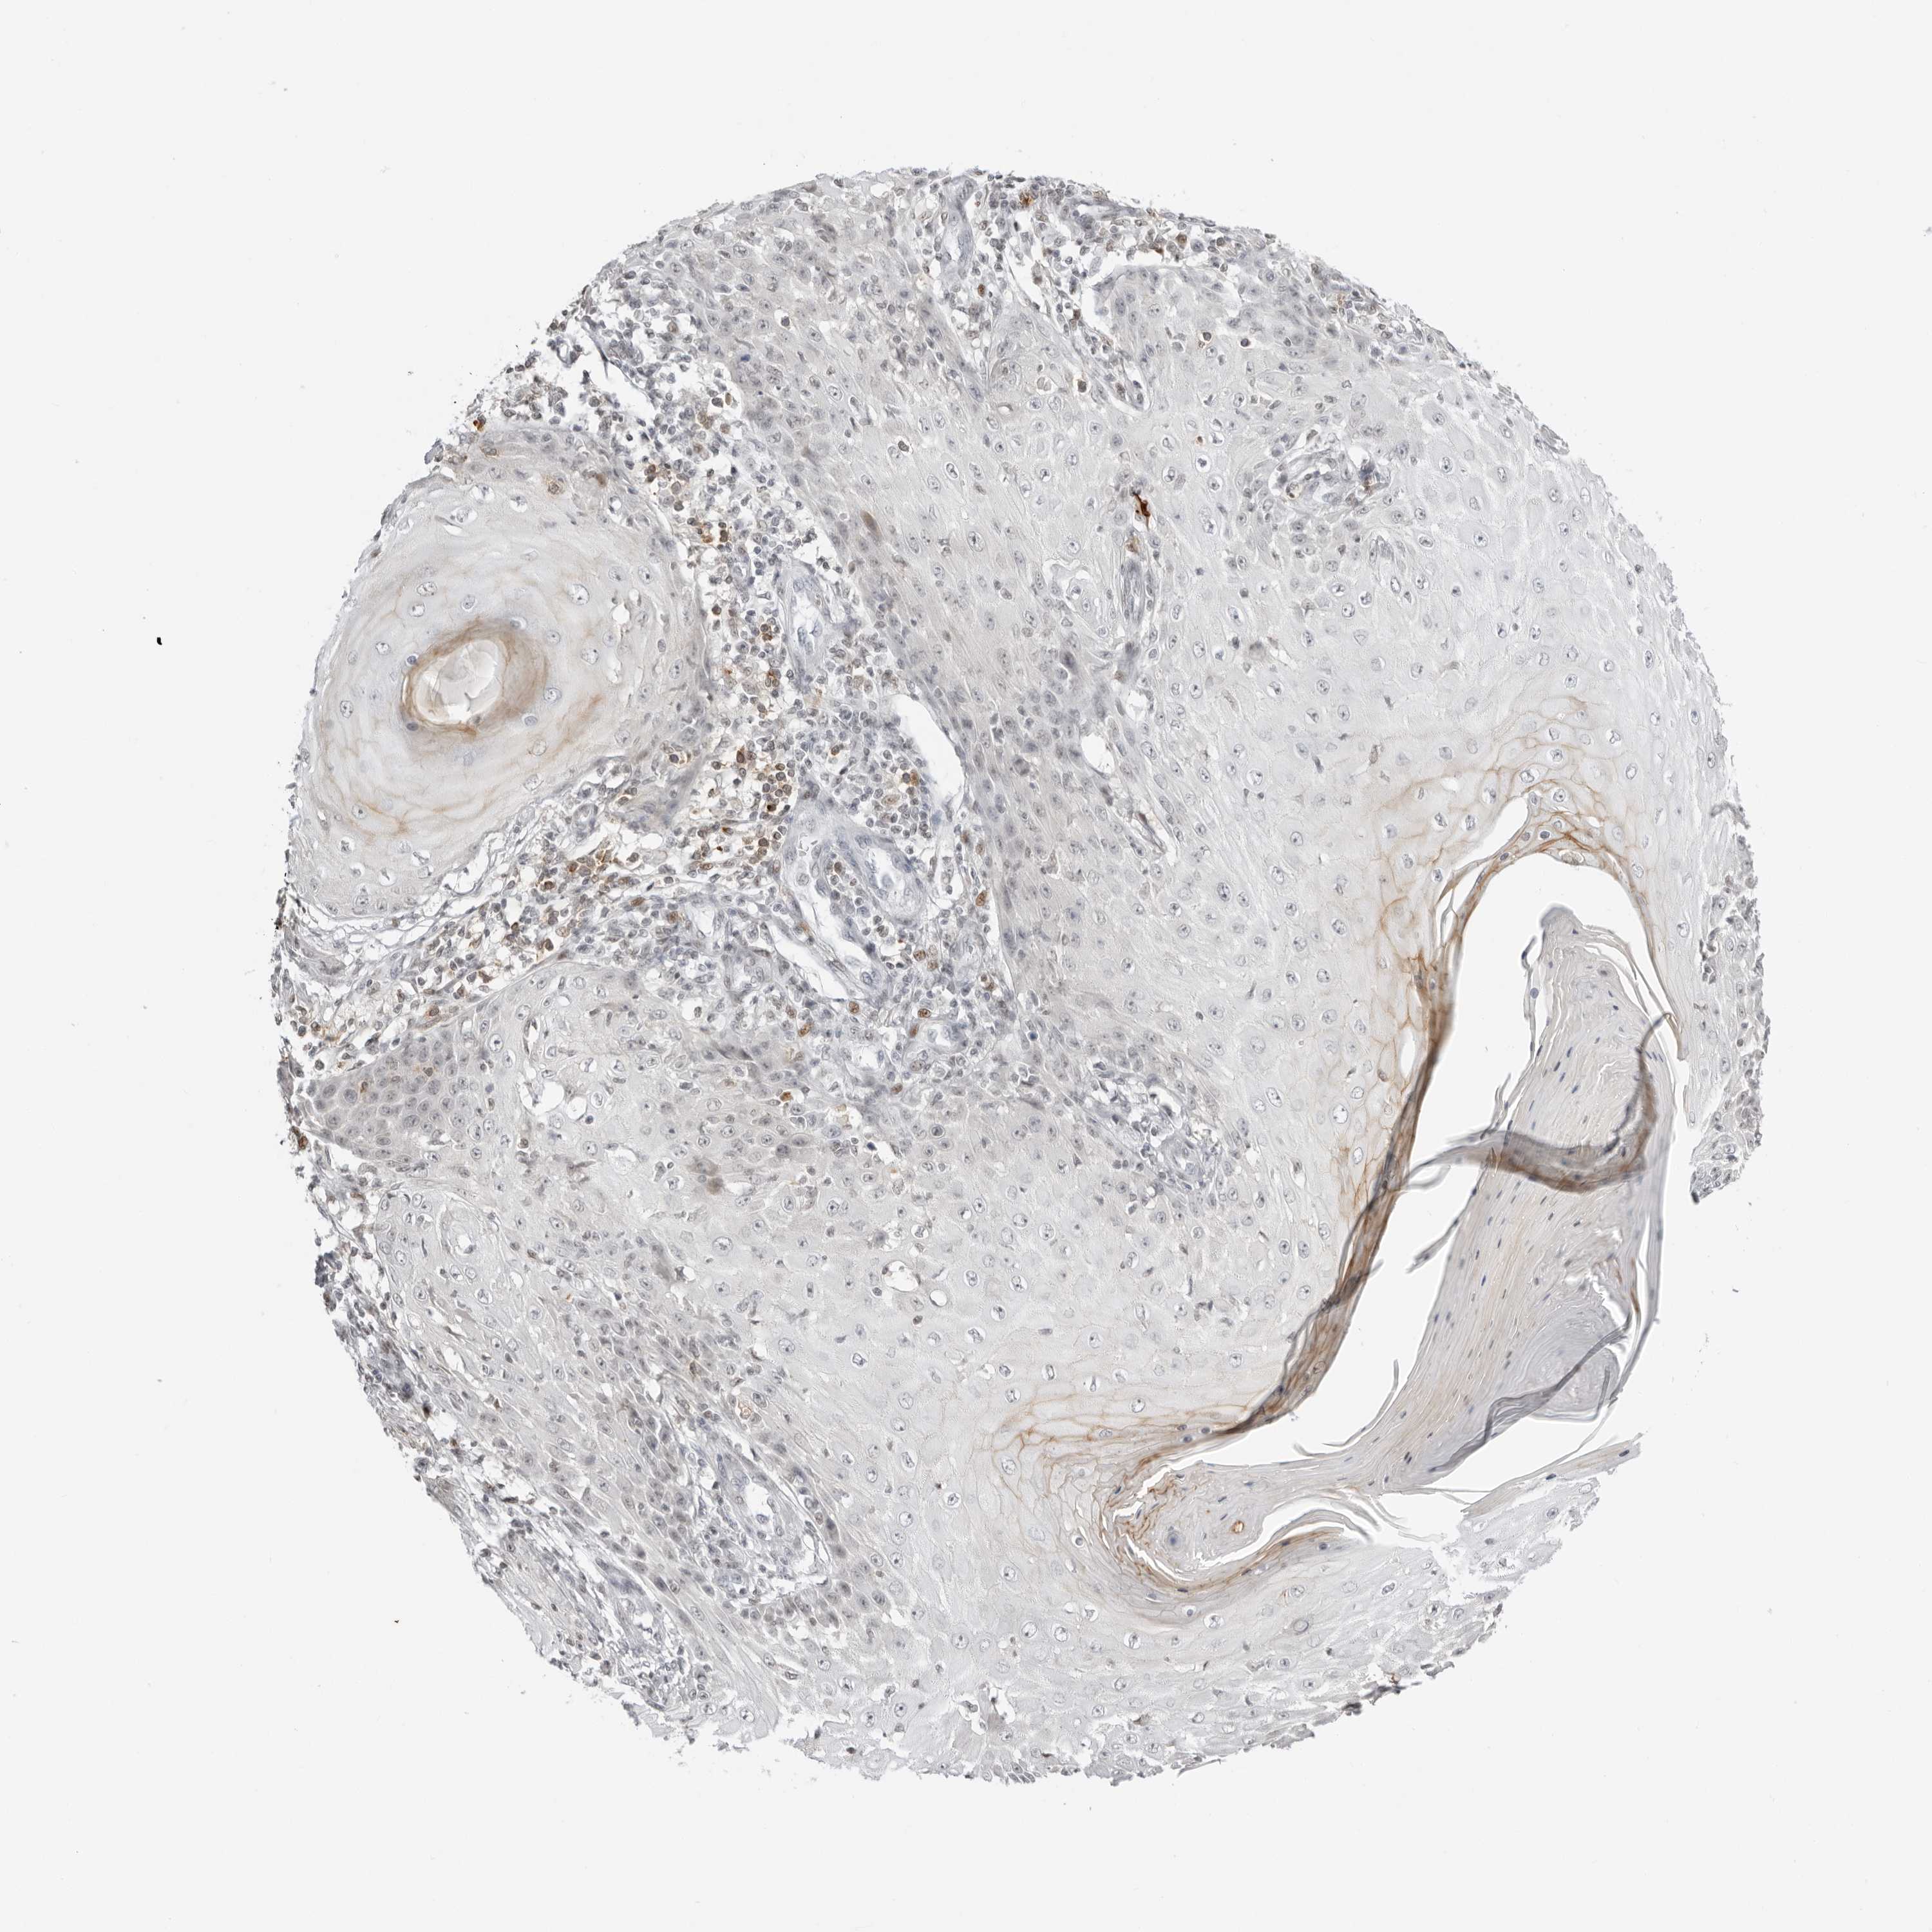

SKIN CANCER - Protein expressioni

A mouse-over function shows sample information and annotation data. Click on an image to view it in a full screen mode. Samples can be filtered based on level of antibody staining by selecting one or several of the following categories: high, medium, low and not detected. The assay and annotation is described here.

Antibody staining in the annotated cell types in the current human tissue is reported as not detected, low, medium, or high, based on conventional immunohistochemistry profiling in selected tissues. This score is based on the combination of the staining intensity and fraction of stained cells.

Each image is clickable and will lead to virtual microscopy that enables deeper exploration of all samples and also displays staining intensity scores, fraction scores and subcellular localization as well as patient and tissue information for each sample.

Antibody HPA027158

Antibody HPA027209

Basal cell carcinoma

Squamous cell carcinoma, NOS

Squamous cell carcinoma, metastatic, NOS